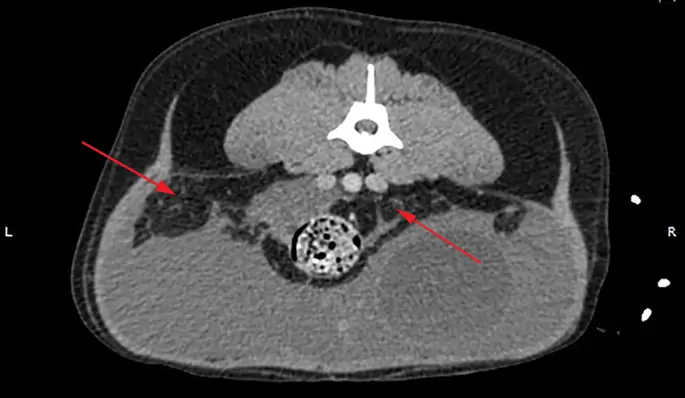

Выполнена контрастно-контрастная томография торакоабдоминальной компьютерной томографии (КТ). В грудной полости мягкий ателектаз клинического значения не обнаружен, в то время как в брюшной полости обнаружен большой объем эхогенной перитонеальной жидкости без контрастного усиления (рис. 1). На левой стороне мочевого пузыря, внутри очагов асцита, была обнаружена фокальная область усиливающего контраст полосатого материала, прилегающая к нисходящей ободочной кишке, левой бедренной артерии, культи матки и левой стороне мочевого пузыря (рис. 2). Единственный маленький (2.5 мм в диаметре) узелок, ослабляющий мягкие ткани, был обнаружен рядом с селезенкой, дорсально с левой стороны живота. Кистозная структура не была снова удалена, и узелок селезенки был слишком мал, чтобы аспирировать. После этих результатов нашими дифференциальными диагнозами были неоплазия, фибриновый материал или гранулематозное воспаление. В качестве диагностической и терапевтической меры была выполнена вентральная срединная исследовательская лапаротомия от мечевидного отростка до лобка. Большая, тонкостенная, заполненная жидкостью структура была обнаружена в левой части брюшной полости, простираясь от левого забрюшинного пространства, которая расширила дорсальную брюшную брюшину и заставила ее отклониться, чтобы лежать дорсально по отношению к мочевому пузырю. С левой стороны жидкость расширялась в левой боковой связке мочевого пузыря и окружала левый мочеточник (рис. 3). Ножка матки не была вовлечена. Кистозная структура была дренирована, чтобы отличить патологическую стенку кисты от нормальных анатомических структур. Оба мочеточника были обнажены, поэтому они не прилипали к кистозной структуре или дорсальной брюшине. Большая часть стенки кисты (около 90%) была удалена при сохранении почек, мочеточников, мочевого пузыря и внутренней и наружной подвздошной артерии и вены. Никаких дополнительных кистозных образований в забрюшинном пространстве не выявлено, а также не было признаков метастазирования в брюшные лимфатические узлы или органы. Узелок селезенки, видимый при УЗИ брюшной полости, не может быть визуализирован макроскопически. Забрюшинное пространство было сальниковой, чтобы помочь в продолжающемся дренировании. Иссекаемая ткань была представлена на гистологическое исследование. Собака выздоровела незаметно и через 2 дня выписана после операции.

фигура 1

Поперечный разрез брюшной полости на КТ, без контраста. Большое количество свободной брюшной жидкости присутствует. Стрелки указывают на забрюшинное пространство, которое имеет полосатый вид, что свидетельствует о свободной жидкости